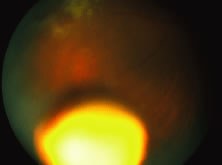

The ARN patient typically presents with progressive visual blurring in one or both eyes occurring over several weeks. These patients often are initially treated with corticosteroids, antitoxoplasmosis drugs, and other medications before arriving at the correct diagnosis. Examination reveals a prominent anterior uveitis that may be granulomatous or nongranulomatous (Fig. 1). Inflammatory signs may be prominent and cause severe pain (Fig. 2). The uveitis may be diffuse and so severe that it causes proptosis. These signs, and the diffuse vitreitis that makes the view of the retina difficult, may contribute to the high degree of delayed and/or misdiagnosis that occurs in the early stages of the disease. Significant vitreous cellular infiltration is seen in the presence of retinitis that is manifest by opacification of the retina, often most prominently in the periphery. Posterior pole involvement may include retinitis, as well as inflammation of the optic nerve head. Optic neuropathy might be the first sign of ARN with subsequent development of other retinal manifestations.8 Ultrasonography and computed tomography (CT) might be helpful in cases of ARN associated with optic nerve edema revealing enlargement of the optic nerve sheath.9 Even in ARN patients who are not immunocompromised and who have no clinical evidence of encephalitis, magnetic resonance imaging of selected cases has shown lesions of the lateral geniculate, optic tracts, and chiasma, which suggests that the virus spreads through the central nervous system (CNS) by axoplasmic transport from the retinal ganglion cells.10 A secondary retinal vasculitis is common, often accompanied by a mild number of retinal hemorrhages. Days to weeks after onset of the infection, the discrete peripheral lesions typically coalesce into a white or yellow ring of infected retina, and the associated vasculature is obliterated (Fig. 3). Necrotic retina desquamates into the vitreous resulting in vitreous sheets.3,6 Eventually, most untreated eyes can be expected to develop retinal detachment resulting from development of multiple full-thickness retinal breaks accompanied by traction or exudation.11 Giant retinal pigment epithelial tears have also been reported.12

A variable number of eyes, up to 75%, develop retinal detachments (Fig. 5). Prophylactic laser for demarcating the areas of active retinitis from normal retina has been advocated to create chorioretinal adhesions that prevent retinal detachments around sites of retinal break formation (which usually occur at the zone between affected and healthy retina). Han and associates43 reported five cases treated with prophylactic laserpexy in addition to antiviral, steroid, and antiplatelet therapy. After 15 months of follow-up, no retinal detachments were noted. Sternberg and coworkers44 described a 75% decrease in the rate of retinal detachment using prophylactic photocoagulation. Some have advocated the creation of a “new ora serrata” by applying confluent rows of laser burns posterior to the areas of retinitis. However, if traction forces from vitreous organization, epiretinal membrane (ERM) formation, or proliferative vitreoretinopathy develop as they commonly do, the contractile forces will be able to overcome any increased chorioretinal adhesion created by the laserpexy. However, McDonald and associates45 reported failure of prophylactic peripheral laserpexy to prevent retinal detachment in ARN patients. In addition, many cases of ARN result in a severe vitritis, limiting the view for a planned laserpexy (Fig. 6). Therefore, vitrectomy with endolaser and concomitant encircling of the eye with a scleral buckle to reduce traction may be required in some patients.46,47 Decisions relating to the need for scleral buckling to support retinal breaks and the use of silicone oil or long-acting gases to repair retinal detachments should be made by an experienced vitreoretinal surgeon.40,48 Selection of cases to undergo operation should be made with consideration given to optic nerve function, visual potential, and medical control of retinitis.